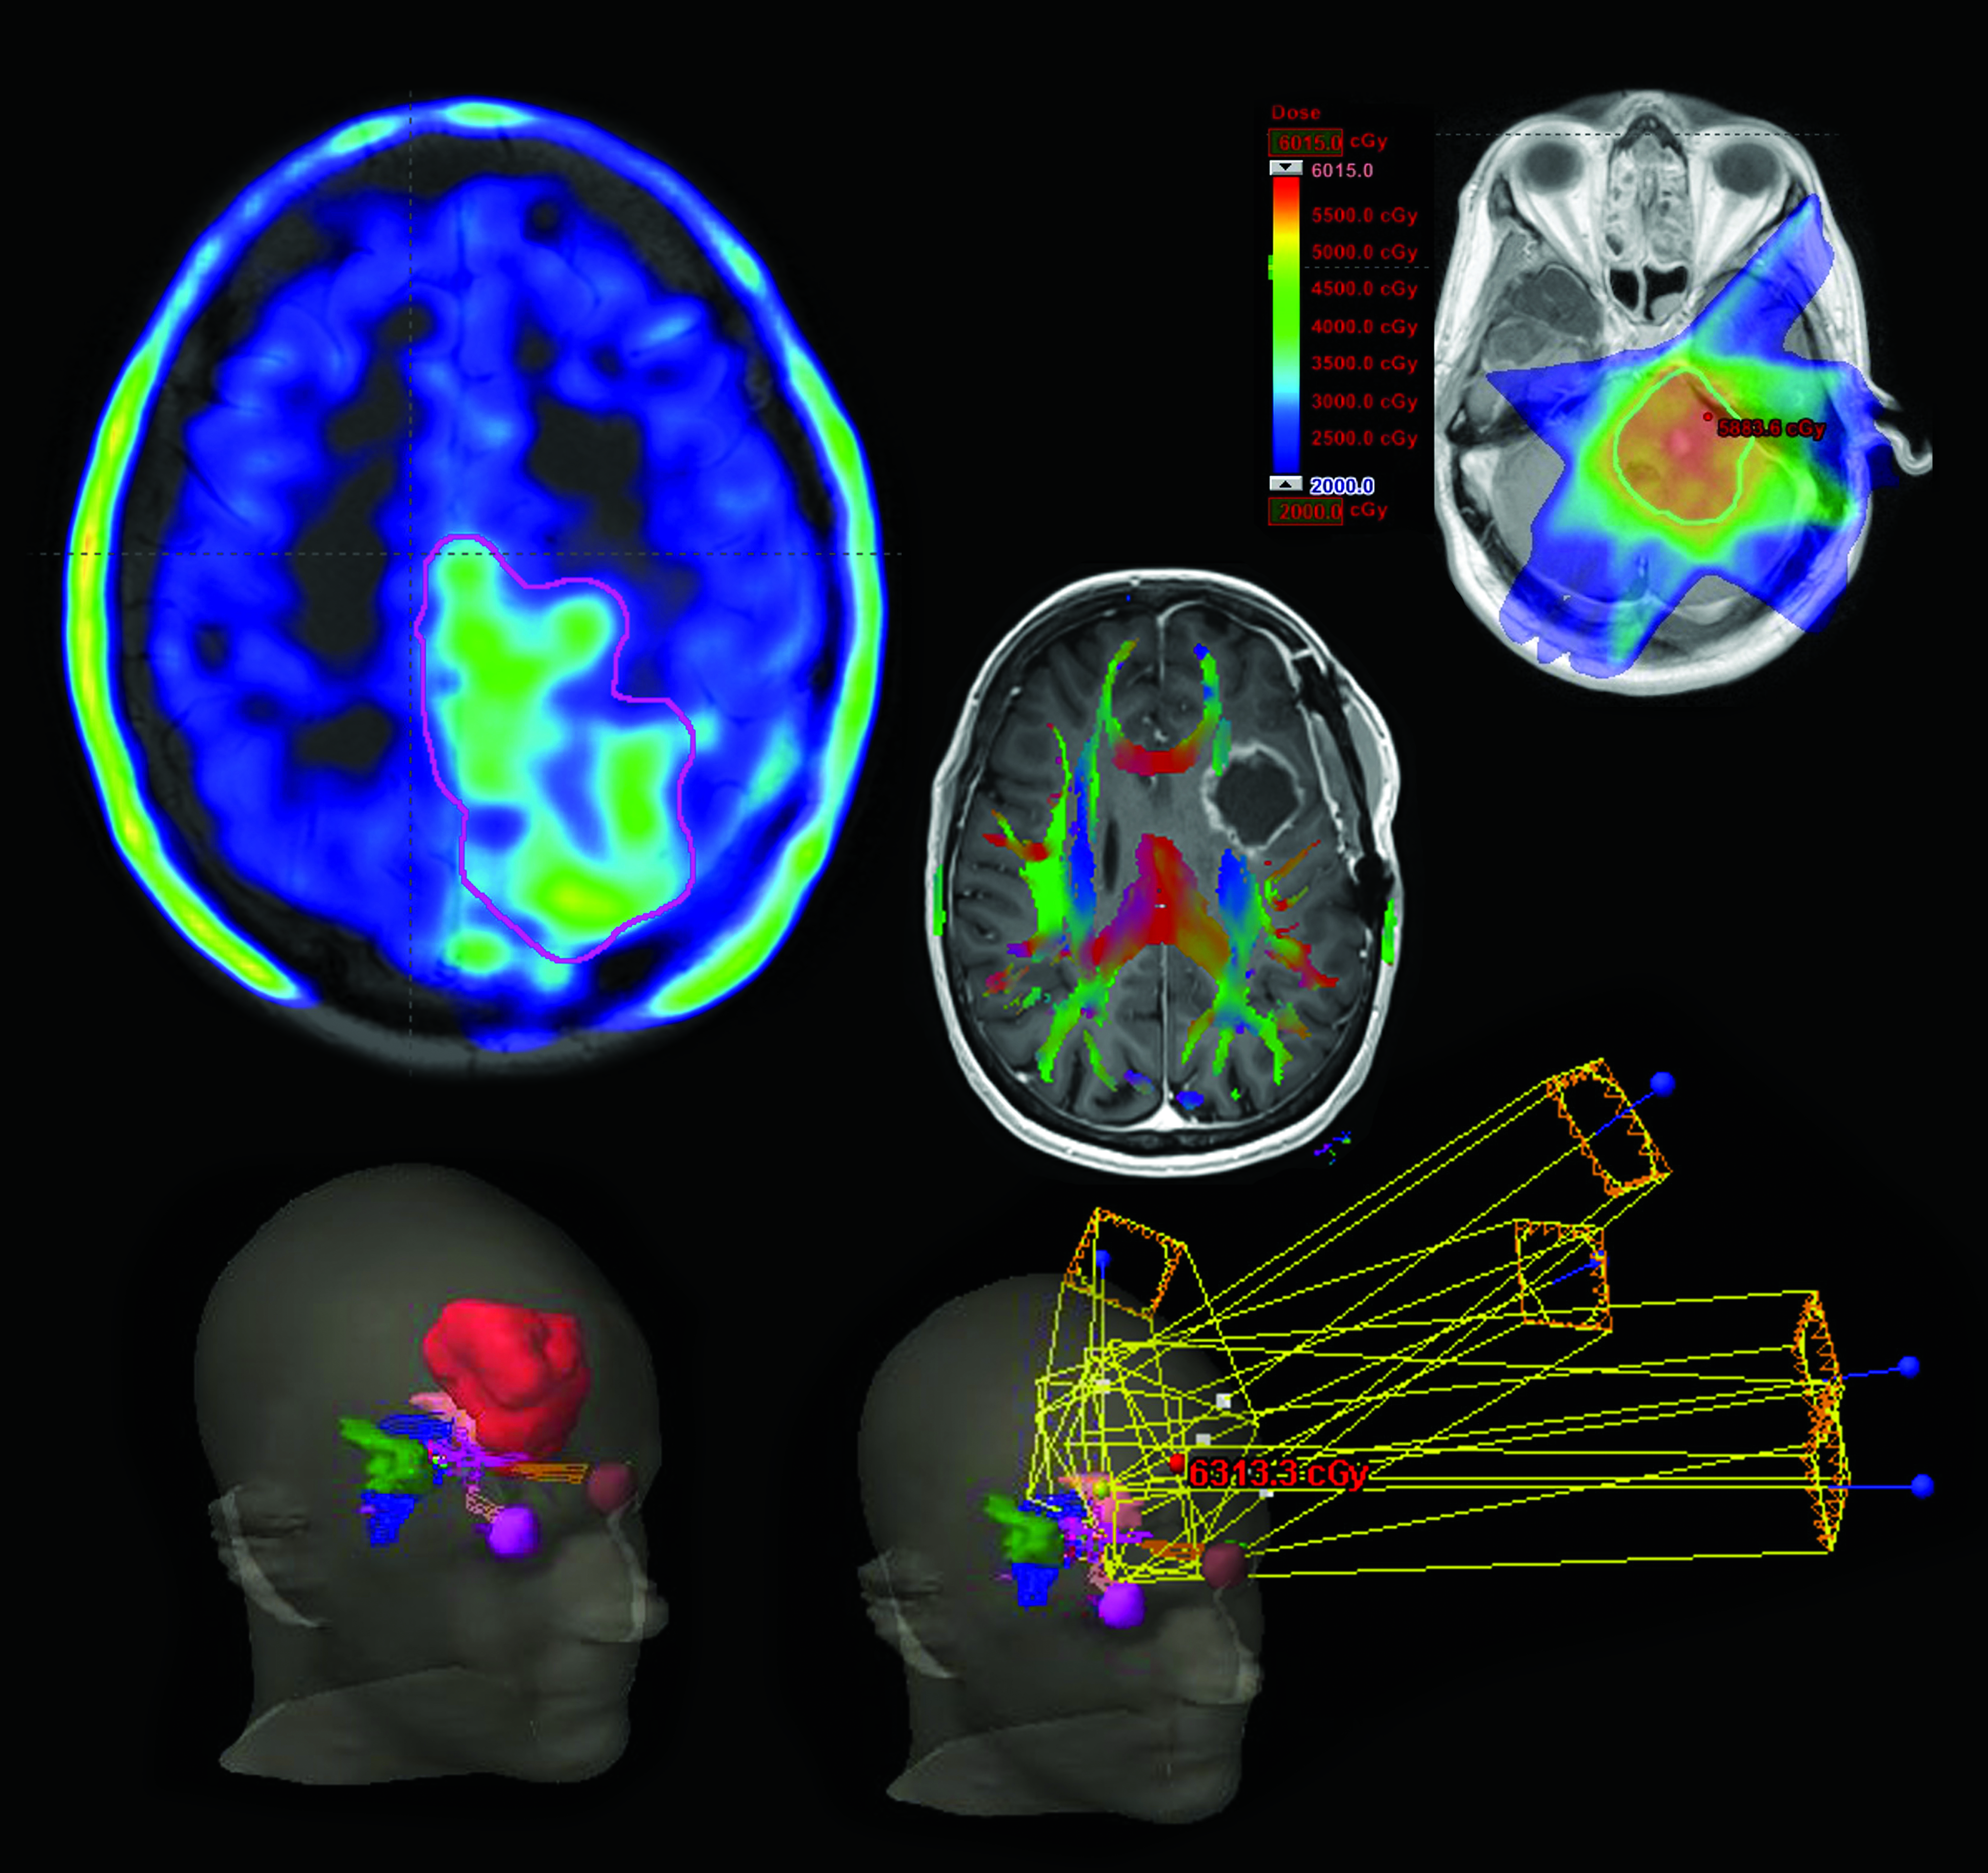

From www.aaroncohen-gadol.com

Brain Tumor Expert Surgeon Aaron CohenGadol MD Medical Imaging For Brain Cancer Modern imaging techniques, particularly functional imaging techniques that interrogate some specific aspect of. mri is undoubtedly the cornerstone of brain tumor imaging, playing a key role in all phases of patient. Medical imaging relies on sophisticated technologies to visualize internal structures within the body, greatly assisting in. It is essential to be familiar with advanced mri—perfusion, diffusion, spectroscopy, and. Medical Imaging For Brain Cancer.